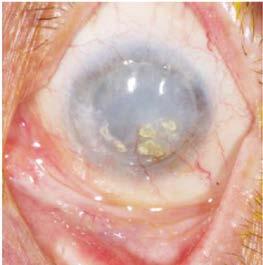

Figura 1. Imágenes de un paciente varón de unos 30 años con diabetes tipo 2 mal controlada (hemoglobina A1c >12%) y sin atención ocular previa. La angiografía con fluoresceína en la cita inicial mostró áreas extensas de ausencia de perfusión periférica con frondas de neovascularización (se muestra el ojo izquierdo). La OCT mostró edema macular diabético grave que afecta al centro (arriba, a la derecha) que respondió bien a las inyecciones intravítreas de anti-VEGF (aflibercept) (abajo, a la derecha). Un año después de la presentación, tenía 20/20 en ambos ojos con una A1c <7% debido a una mejor adhesión al cuidado de la diabetes y un mejor control sistémico de la glucosa.  Foto. Ian C. Han, MD.

Se reevalúa la paciente encontrando persistencia de la diaforesis, palidez mucocutánea y marcada fotofobia. A nivel ocular derecho se encuentra córnea opaca, midriasis media de 7 milímetros, reactiva y presión digital alta, con imposibilidad de evaluar estructuras del fondo por opacidad de medios (Figura 1). En ojo izquierdo, se encuentra conjuntiva tranquila, córnea transparente, cámara anterior panda, tonometría digital media, pupila de 3 milímetros reactiva a la luz, cristalino transparente y al fondo de ojo excavación de 0.3, anillo neurorretiniano sano y mácula sana (Figura 2).

Figura 1. Ojo derecho con opacidad corneal y midriasis media arreactiva.